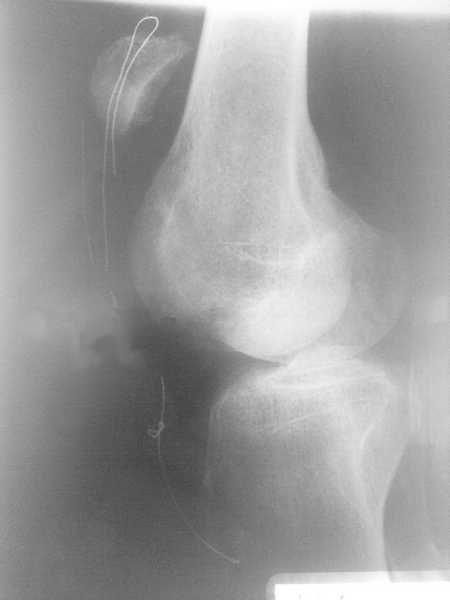

Пациент О 49 лет. получил многооскольчатый перелом н/полюса надколенника 17.06.09.

по поводу чего была выполнена резекция полюса и наложена проволочная петля. 8 октября повторная травма. Уважаемые коллеги, подскажите что делать.